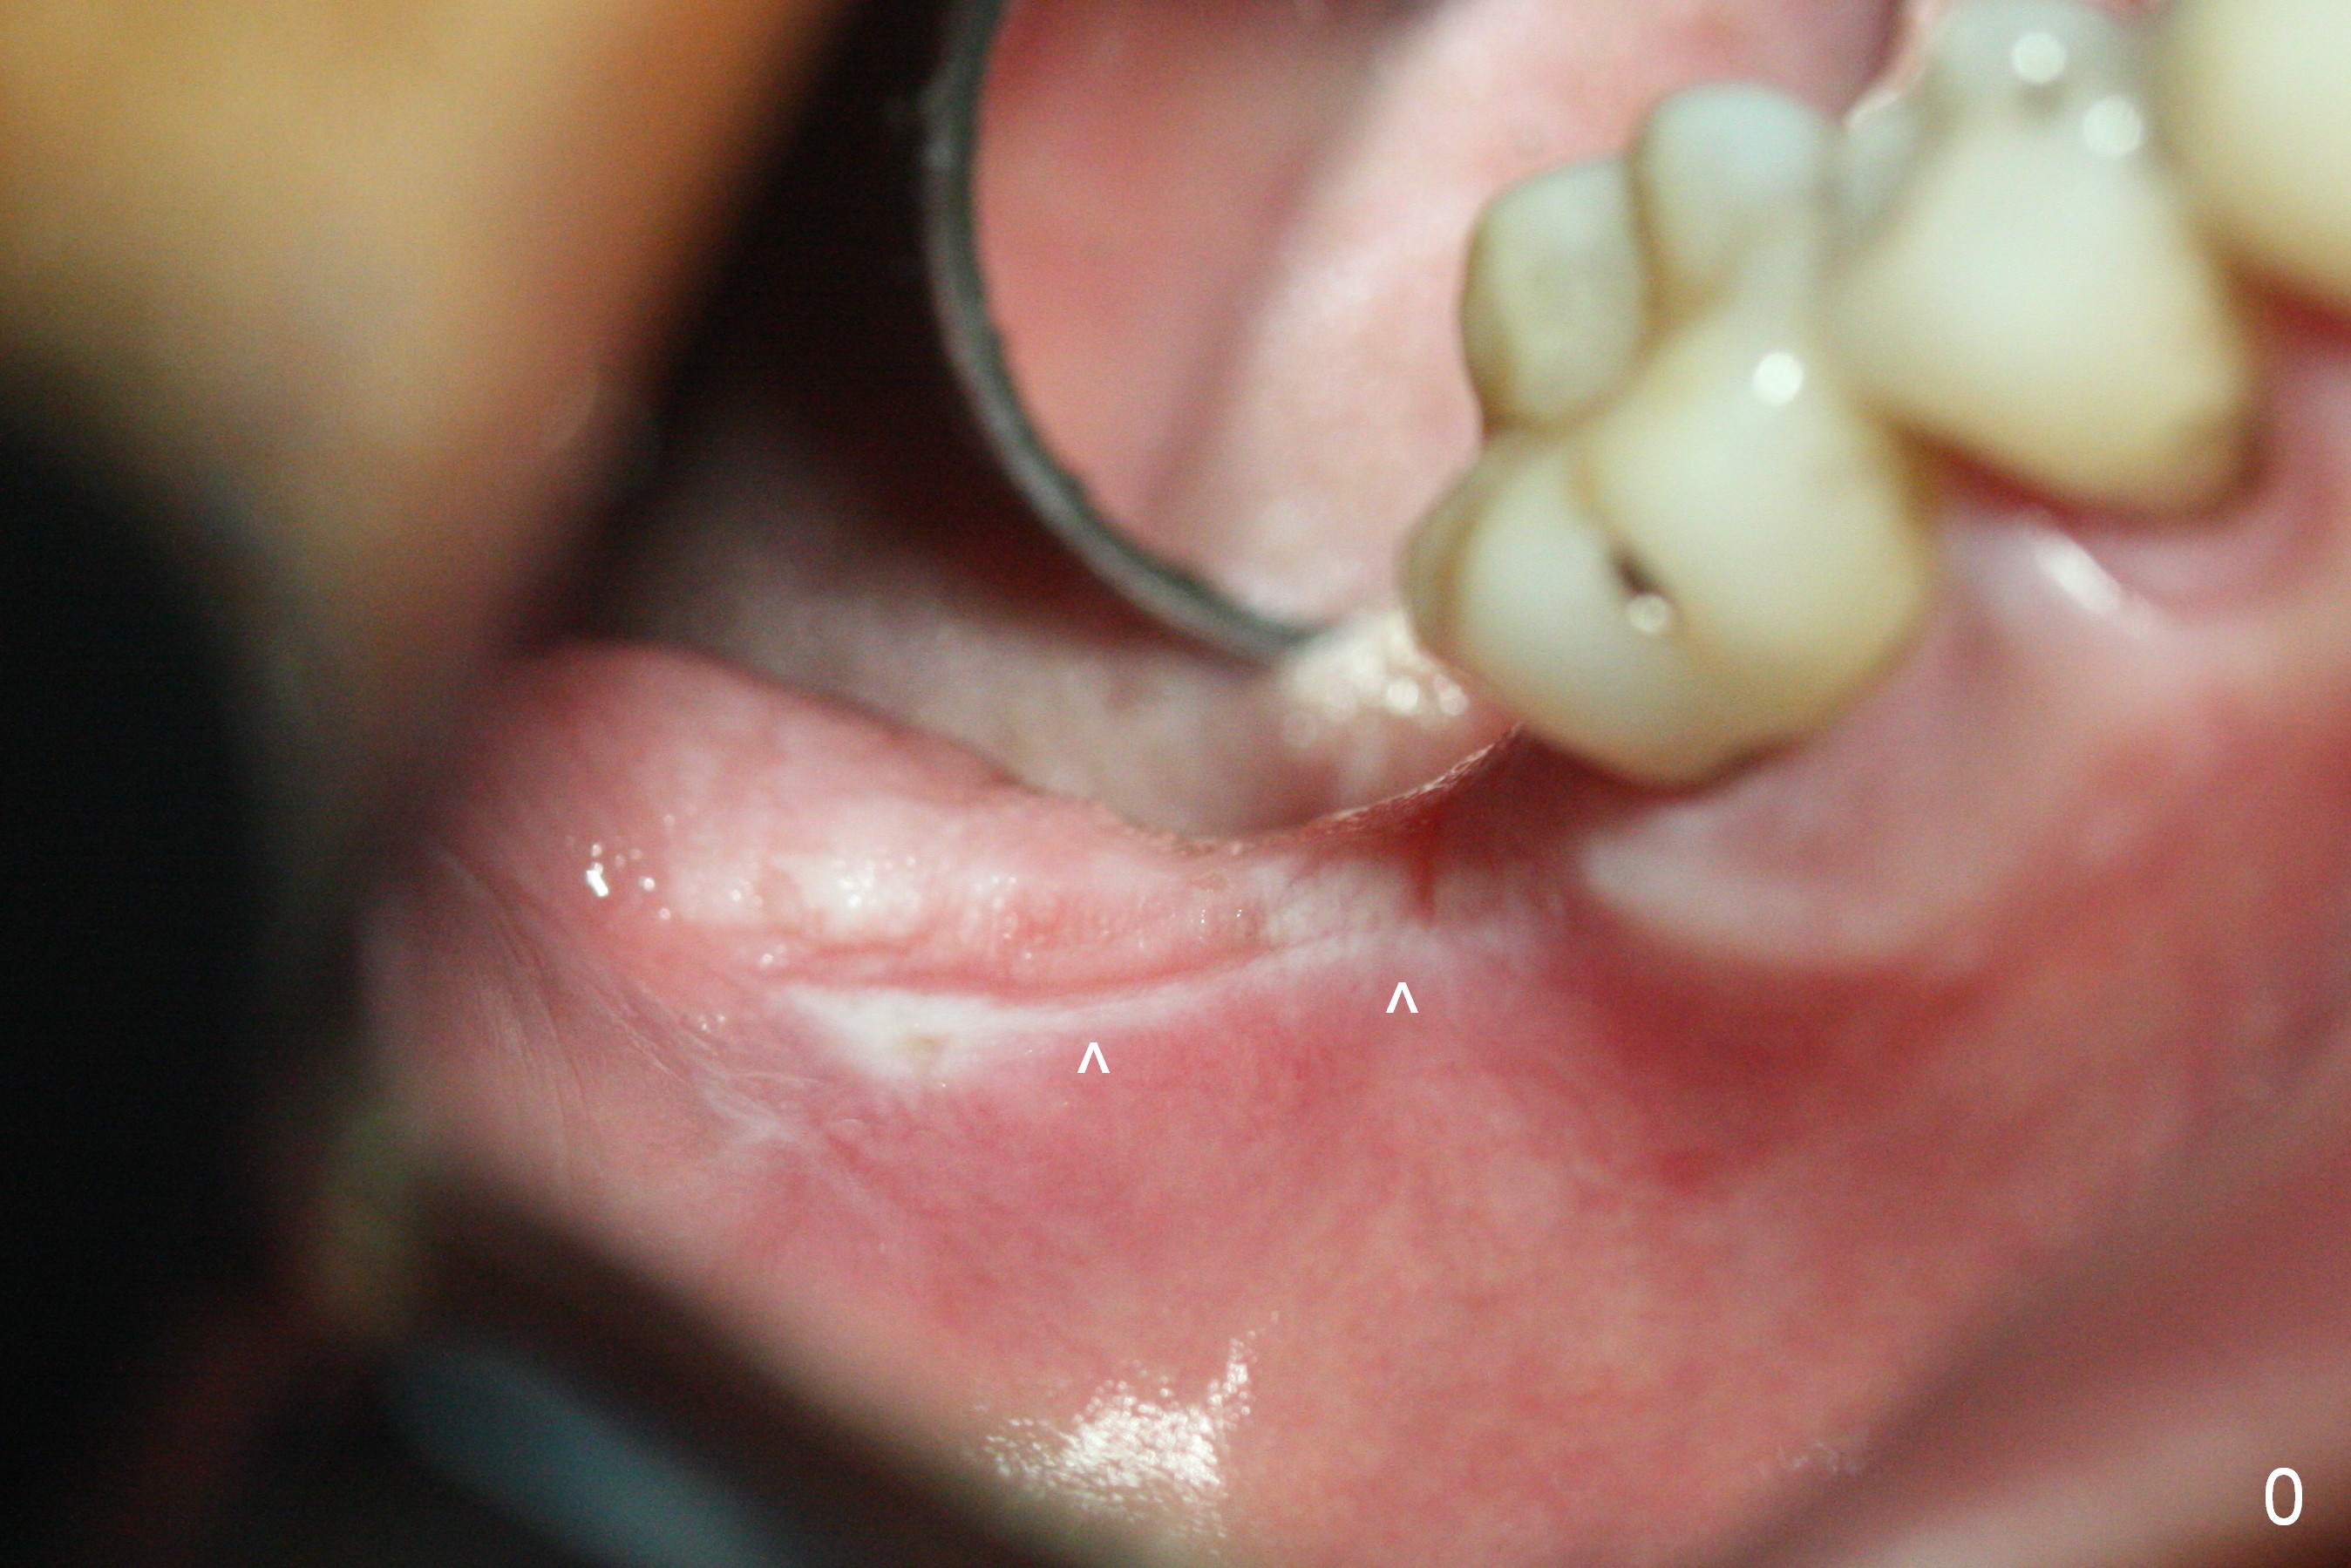

The leukoplakia at the sites of #31 and 32 is most likely related to smoking and the supraerupted teeth #1 and 2 (Fig.0 ^).  After osteotomy for 11.5 mm at #31 (Fig.1), it appears that the bone height is not as much as expected.  The last two drills for sequential osteotomy are 4.3x13 and 4.8x11.5 mm.  A 5x11.5 mm UF implant is placed slightly subcrestal with insertion torque > 50 Ncm (Fig.2).  Following placement of 6.5x2 mm healing abutment, the opposing tooth needs adjustment for height.  Orthodontic intrusion of the opposing tooth is scheduled 2 days later.  It is accidental to find root fracture of the mesial root of the tooth #30 (Fig.1 <).  There is minimal bone resorption coronally 5 months postop (Fig.3).  A provisional is fabricated at #31 to assist in intrusion of the tooth #2.  A crown is cemented 11.5 months postop (Fig.4); the leukoplakia at #31 seems to lessen.  The tooth #30 is lost during the pandemic, followed by looseness of the crown and abutment at #31.  When the complex is reseated, the occlusal scheme is changed, suggesting incomplete seat of the abutment earlier (Fig.5).